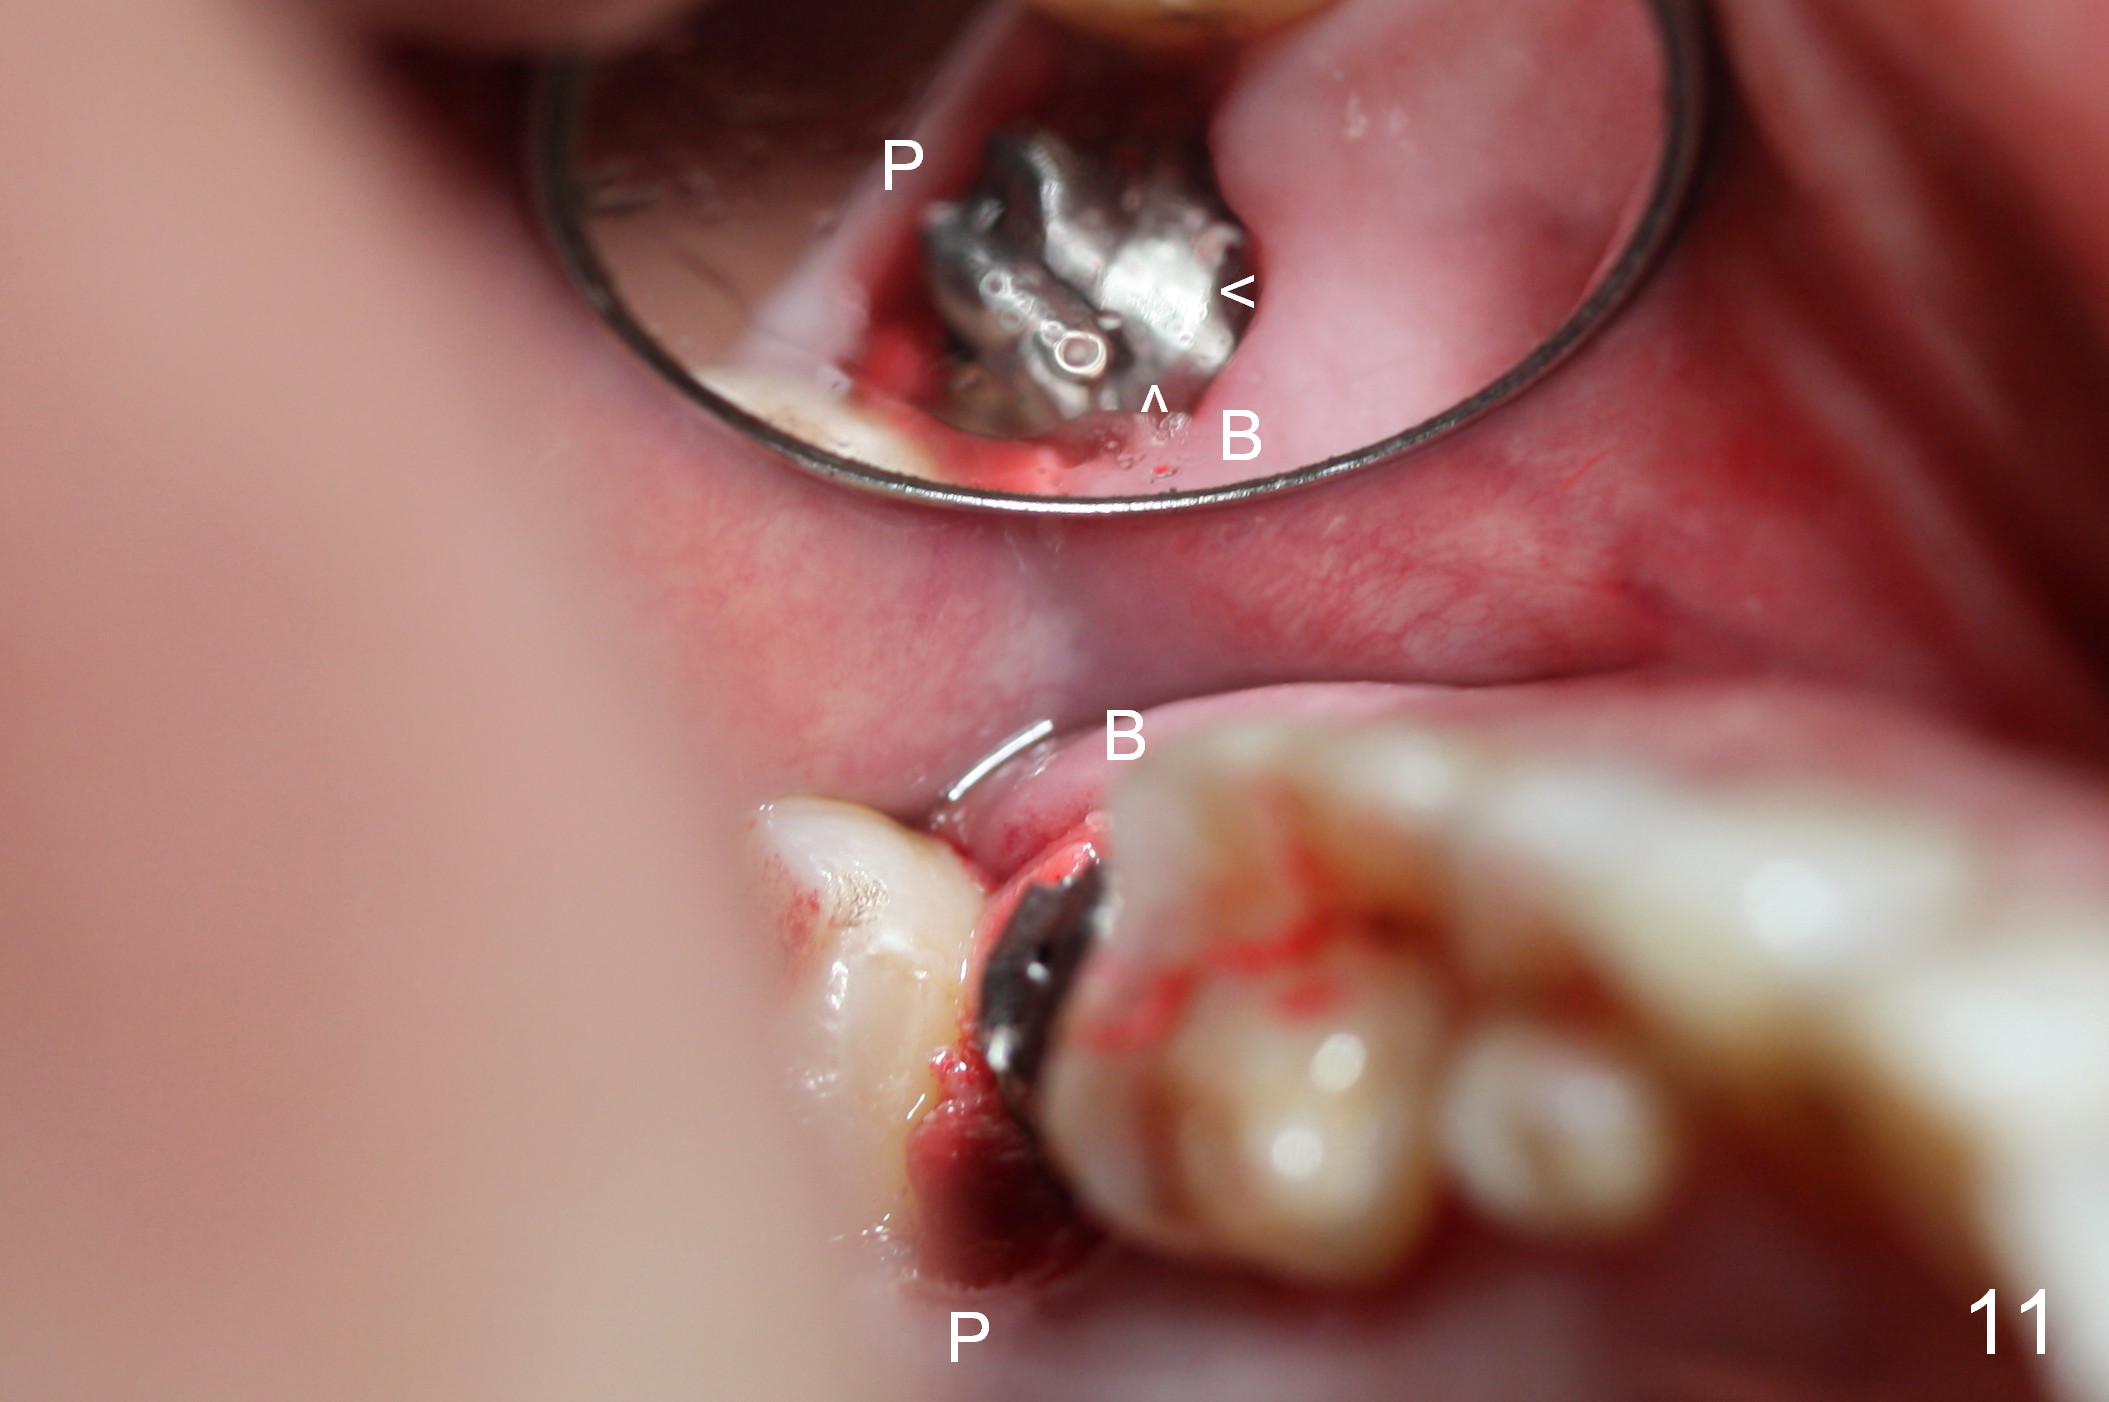

Probably due to bruxism, there is limited vertical restorative space. The margin is subgingival except buccal (Fig.10,11). An immediate provisional (Fig.12 P) appears to have to be fabricated to prevent soft tissue from covering the margin during osteointegration. It is our intention to make gingival envelop larger than the definitive crown cervix. It would be easier to remove a permanent cement later on for peri-implantitis prevention.

The patient returns because of provisional dislodgement 4 days postop. It appears that the socket shrinks (Fig.13 mirror view) with partial resolution of collagen dressing (*, as compared to Fig.10). The provisional is relined and reseated with occlusion checked (Fig.14). There is no sign or symptom of infection. The patient is pleased.